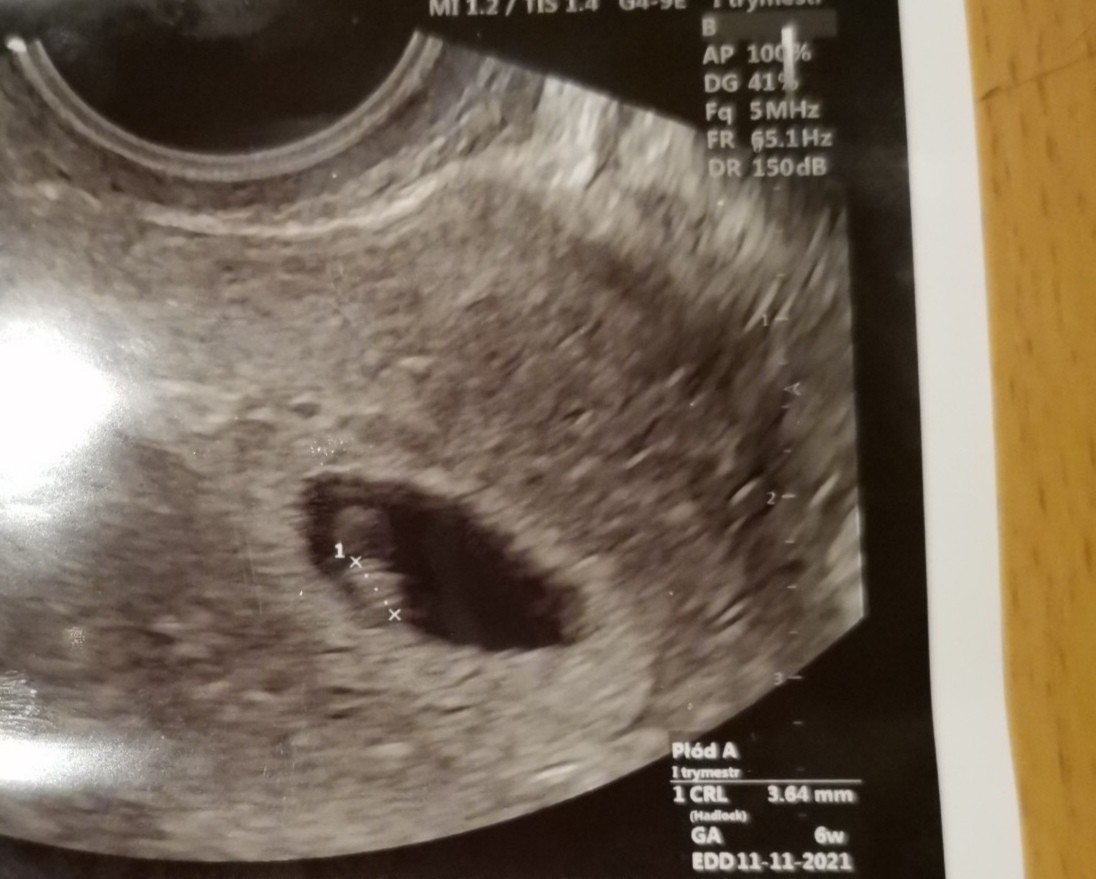

Jestem po wizycie u gina.

Dzisiaj 6w0d, pęcherzyk ciążowy jest, zarodek 3,64mm i serduszko pięknie biło 💖💖💖

Załączniki

• IMG_20210318_191516.jpg

IMG_20210318_191516.jpg

133,3 KB · Wyświetleń: 115